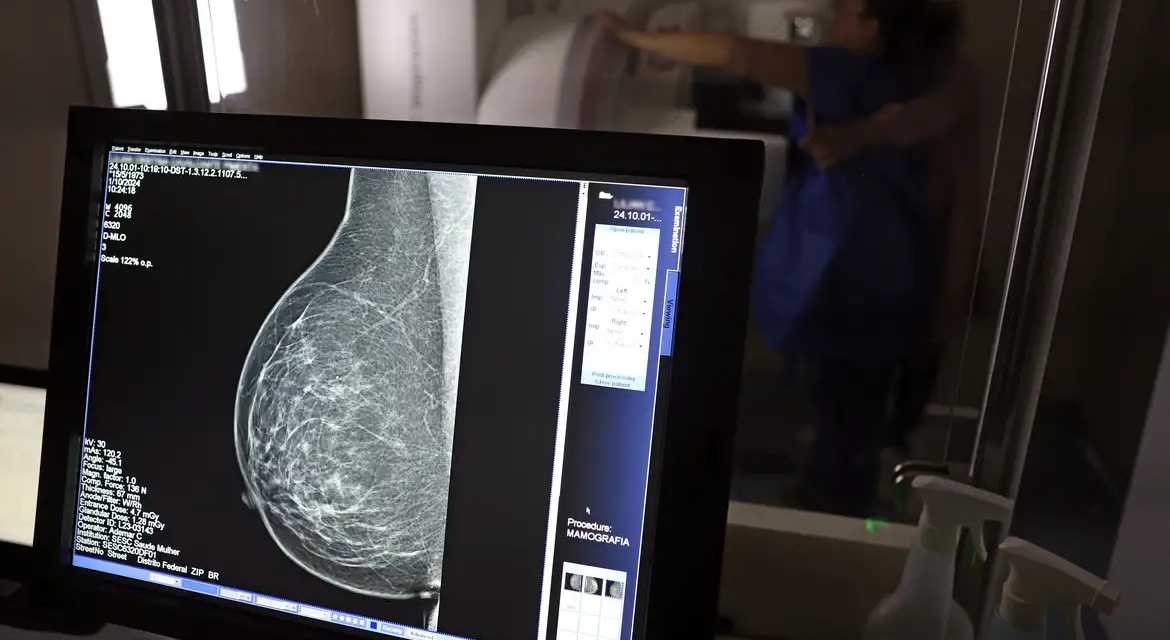

No mês de conscientização sobre o câncer de mama, um relatório destaca a importância de acesso igualitário ao rastreamento e tratamento da doença. Segundo o Atlas da Radiologia no Brasil, do Colégio Brasileiro de Radiologia e Diagnóstico por Imagem (CBR), o acesso aos mamógrafos ainda é um desafio.![]()

O país tem 6.826 equipamentos registrados, sendo 96% em funcionamento. Metade deles está disponível no Sistema Único de Saúde (SUS), responsável por atender 75% da população. Isso equivale a 2,13 mamógrafos por 100 mil habitantes dependentes do SUS.

Na saúde suplementar, que cobre 25% da população, o cenário é mais favorável: 6,54 aparelhos por 100 mil beneficiárias, quase o triplo da rede pública. O Acre exemplifica essa disparidade — são 35,38 mamógrafos por 100 mil habitantes na rede privada, contra 0,84 no SUS.

Há disparidades regionais. Roraima tem a menor proporção (1,53 por 100 mil), seguida do Ceará (2,23) e Pará (2,25). A Paraíba lidera o ranking (4,32), à frente do Distrito Federal (4,26) e do Rio de Janeiro (3,93).

O Brasil tem uma cobertura muito baixa de mamografias: 24%. O ideal recomendado pela Organização Mundial da Saúde é de 70%. Mesmo em lugares como o estado de São Paulo, que tem a maior concentração de mamógrafos do país, a taxa gira em torno de 26%.

Em setembro, o Ministério da Saúde ampliou as diretrizes de rastreamento, recomendando que mulheres entre 40 e 49 anos realizem mamografias, mesmo sem sintomas. De acordo com o Instituto Nacional do Câncer (Imca), mais de 73 mil mulheres recebem o diagnóstico de câncer de mama anualmente no Brasil.